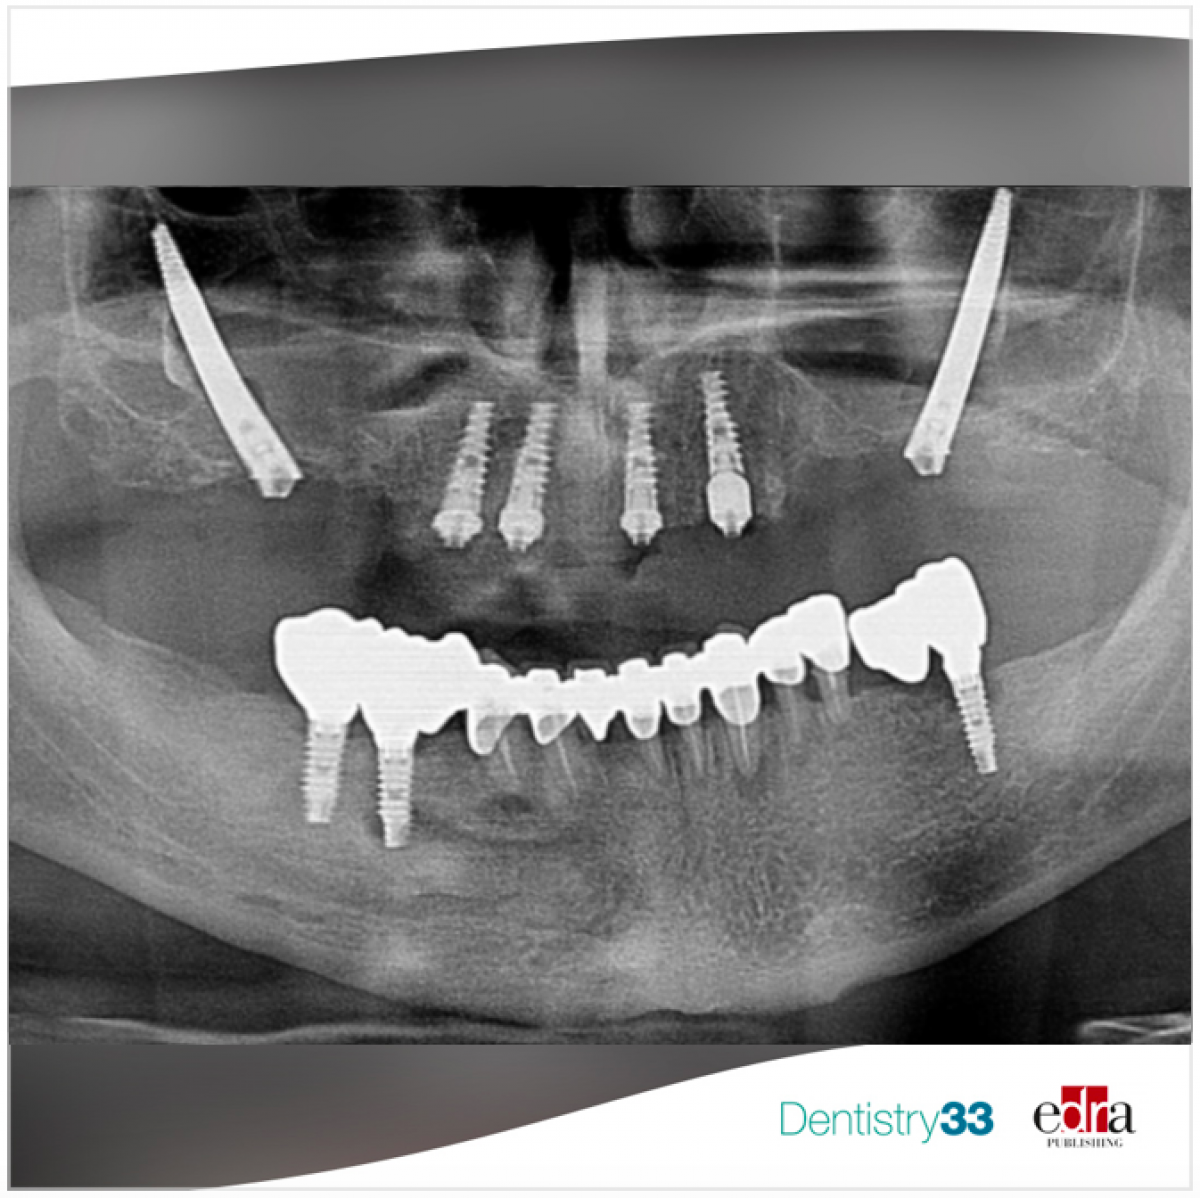

Male 59 year old patient, non smoker, with no evidence of systemic diseases.

The patient presents a superior provisional bridge anchored on three dental pieces 1.2,1.1, 2.3 and on an implant in 2.4.

Additionally, ha has two implants in 1.4 and 1.5 with fractured prosthetic connections that can!t be considered useful anymore.

The dental pieces (1.2, 1.1, 2.3) present a mobility grade III and the implant in 2.4 shows an hori- zontal bone resorption of 4/5mm and previous abscesses.

In the posterior sectors a severe bone atrophy can be observed. FIG 1